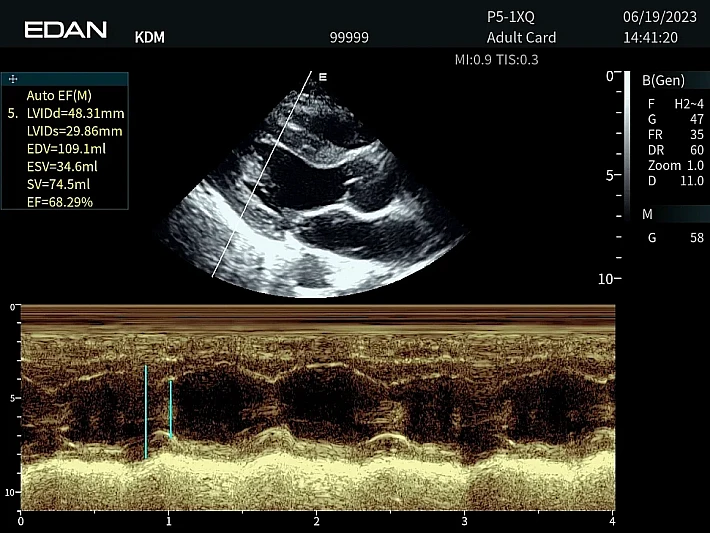

Медицинское оборудование и сервисное обслуживание